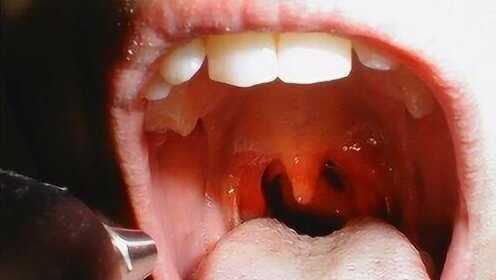

慢性咽炎概述

慢性咽炎是一種常見的喉部疾病,主要表現為咽部不適、干燥、瘙癢、疼痛等癥狀,由于長期受到刺激或感染,咽部黏膜出現慢性炎癥表現,慢性咽炎雖然不是嚴重疾病,但癥狀反復發(fā)作,嚴重影響患者的生活質量。